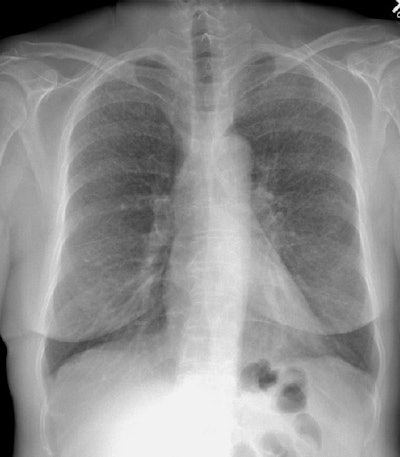

The patient was an male smoker who presented with complaints of increasing difficulty with physical fitness training and a cough. The chest radiograph demonstrated a diffuse symmetric upper and middle lung reticulonodularity which spared the lung bases and the lung volumes were normal (Click here to see a coned view). Lung biopsy confirmed the diagnosis of Langerhans cell histiocytosis.